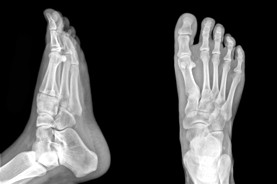

The Foot Institute is an association of Fort McMurray Doctors specializing in the medical treatment of the foot and ankle, and is one of the largest groups of foot specialists in Alberta.

The Fort McMurray Foot Institute is dedicated to the medical and surgical treatment of the foot. Our mandate is to provide the best possible medical, surgical and preventative treatment available for our patients. We do this by providing well-trained Doctors who are committed to treat and prevent all types of foot pain, biomechanical disorders, as well as all other problems relating to the feet.

At the Fort McMurray Foot Institute, our Doctors are trained to specifically treat problems associated with your feet or ankles. Below are several of the most common problems that we see on a day to day basis: